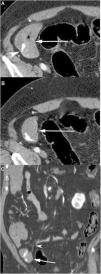

The presence of an MD in a MDCT should be suspected when a blind tubular structure connected to the terminal ileum by a neck of variable size is observed. Multiplanar 2D reconstructions images and CT enterography can help in the diagnosis. In patients with symptoms of obstruction or intestinal inflammation, the possibility of a complication secondary to a MD should be considered, especially when the terminal ileum and the vermiform appendix are normal. MDCT angiography, in cases of acute gastrointestinal bleeding, can identify contrast extravasation and accumulation of blood in the MD, and could demonstrate the persistent omphalomesenteric artery, which is diagnostic of MD. Other MDCT findings such as the presence of enteroliths or associated inflammatory changes around the MD can facilitate the preoperative diagnosis of MD complications.